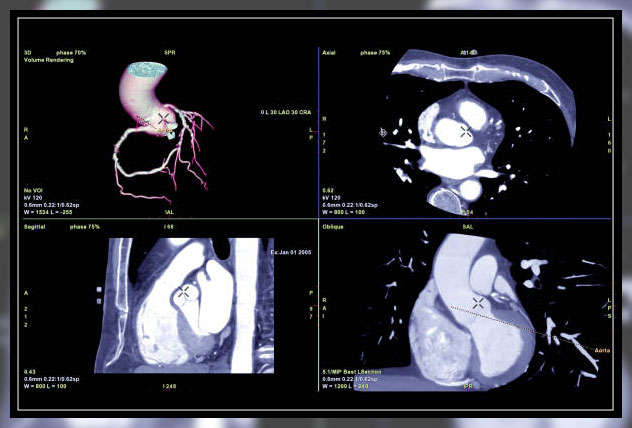

Doctors often use an MRI or CT scan before performing the procedure of a coronary angiography test.

This is in an effort to pinpoint problems with the heart of a patient.